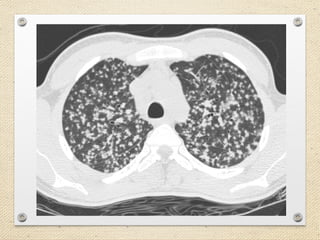

Chest CT scanning

• Chest CT scanning has higher sensitivity and

specificity than chest radiography in displaying well-

defined randomly distributed nodules.

• High-resolution CT scanning with 1-mm cuts may

be even better. It is useful in the presence of

suggestive and inconclusive chest radiography

findings.

Chest CT scanning •Chest CT scanning has higher sensitivity and specificity than chest radiography in displaying well- defined randomly distributed nodules. • High-resolution CT scanning with 1-mm cuts may be even better. It is useful in the presence of suggestive and inconclusive chest radiography findings.